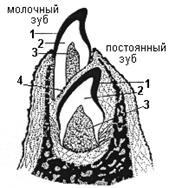

(ранняя стадия развития) - начало 6-7 неделя внутриутробного развития (рис.1

Рис.1.

Закладка зачатка молочного зуба

. 1 - эпителий ротовой полости, 2 - зубная пластинка, 3 - эмалевый орган, 4 - зубной сосочек.

Начинается с погружения эпителия ротовой полости в подлежащую мезенхиму в виде плотного тяжа (зубной пластинки). На зубной пластинке появляются мелкие эпителиальные выпячивания называемые зубными зачатками, из которых (10 снизу и 10 сверху) будет развиваться молочный ЗБ. По мере роста зубной пластинки каждый зубной зачаток увеличивается в размере, глубже внедряется в мезенхиму и принимает форму перевернутой чаши. Эта структура образует эмалевый орган, а нижележащая мезенхима, заполняющая полость чаши, называется зубным сосочком.